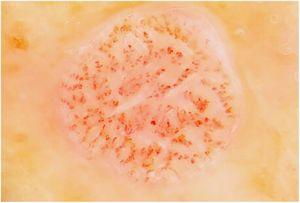

Imágenes perifoliculares radiales y en cabeza de medusa como signo de sospecha de lentigo maligno

R. Gamo Villegas, M.U. Floristán Muruzábal, A. Pampín Franco

Actas Dermosifiliogr. 2023;114:734

Acceso a texto completo

[Translated article] Perifollicular Radial Lines and Medusa Head-Like Structures: Signs Suggesting Lentigo Maligna

Actas Dermosifiliogr. 2023;114:T734